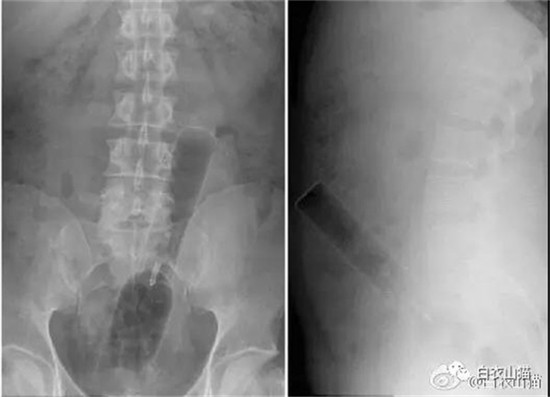

大肠里的擀面杖。男性

这是做饺子皮用的擀面杖。对,全部塞进去了。你知道怎么看男女吗?看骨盆的角度。

取出的方法如同上面。